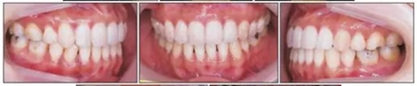

治療后面部和口內(nèi)照片顯示治療結(jié)果很成功(Figure 8)?;颊叩拿嫘瞳@得了非常顯著的改善,尤其是在唇部區(qū)域。覆合從-3.5mm增大到3.5mm,覆蓋從1.2mm增大到2.0mm。獲得了I類磨牙關(guān)系,沒有擁擠(Figures8 and 9)。

全景片顯示上前牙區(qū)未發(fā)生進行性牙根吸收。然而,在下磨牙區(qū)有輕度牙根吸收,并且牙根平行性有改善空間(Figure 10A)。

治療前后頭影疊加圖清楚地顯示,下頜發(fā)生逆時針旋轉(zhuǎn),上下切牙舌側(cè)移動(Figure 11)。CT顯示髁突未發(fā)生形態(tài)改變,而磁共振T2影像顯示有形態(tài)改善(未提供圖像)。在治療期間沒有出現(xiàn)顳下頜關(guān)節(jié)癥狀。

保持2年后,患者的面型和咬合關(guān)系獲得了良好的維持,并且患者對治療結(jié)果非常滿意(Table 1, Figure 12)。任一側(cè)都沒有出現(xiàn)顳下頜關(guān)節(jié)紊亂情況。